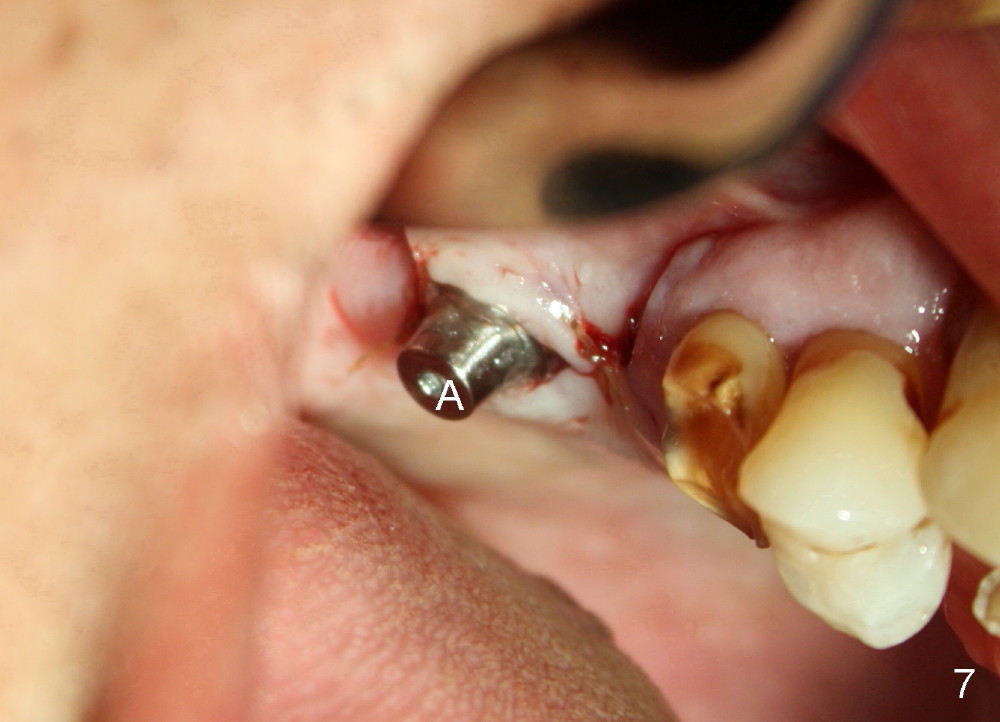

The flaps do not completely contact the implant when they are sutured. The wound needs protection during the initial postop stage. One of modes is to use perio dressing. The latter is not retentive in the distal edentulous area. Addition of a short abutment (Fig.7 A) over the implant should increase the retention of perio dressing (Fig.8) while micromovement of the implant is minimal. The tooth #30 is missing. There is no bone resorption 2 years 11 months post cementation (Fig.9).